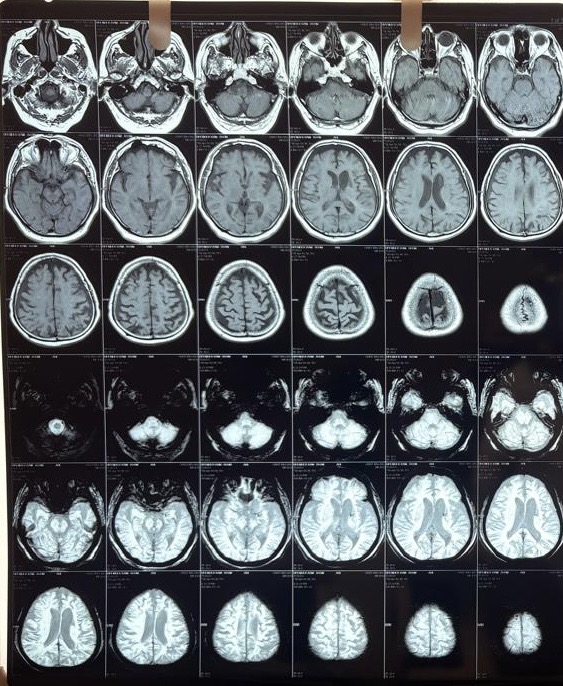

MRI Brain (April 2026)

This was the critical investigation. The MRI brain with DWI (diffusion-weighted imaging), FLAIR, and T2 sequences revealed a layered, complex picture:

Acute ischemic infarct:

A small area of diffusion restriction with low ADC values (a pattern on MRI that indicates fresh, actively dying brain tissue) was identified in the left deep parieto-temporal region, measuring approximately 1.1 x 0.6 cm. This confirmed an acute ischemic stroke (a new blockage of blood supply to a specific brain region) was occurring at or around the time of presentation.

Subacute/chronic left parietal infarct:

A larger heterogeneous T2/FLAIR hyperintense lesion in the left high parietal region (approximately 3.1 x 3.3 cm) showed mixed features: internal gliotic areas with CSF FLAIR suppression, irregular peripheral diffusion restriction with high ADC values, overlying cortical atrophic changes, and subcortical gyriform T1 hyperintensities. This pattern was consistent with sequelae of a subacute to chronic prior infarct with cortical laminar necrosis (scarring of the cortical surface following prolonged ischemia))*; indicating a prior stroke that had likely gone undiagnosed.

Old lacunar infarcts:

Multiple small gliotic lacunar infarcts (tiny old stroke scars from small vessel disease) were seen bilaterally in the corona radiata and ganglio-capsular regions, the largest approximately 7.7 x 2.8 mm in the left anterior ganglio-capsular region.

White matter disease:

Bilateral periventricular and centrum semiovale T2/FLAIR hyperintense white matter foci without diffusion restriction, consistent with chronic microvascular ischemic changes (long-standing small vessel damage due to diabetes and hypertension).

Cerebral and cerebellar atrophy:

Diffuse senile atrophy (age-related brain shrinkage) was noted across both cerebral hemispheres, most prominent in the fronto-parietal regions, along with mild cerebellar atrophy. This contributed to the cognitive picture.

The brainstem, basal ganglia, thalami, internal capsules, major intracranial vessels (flow voids), and cerebellopontine angles were all intact.